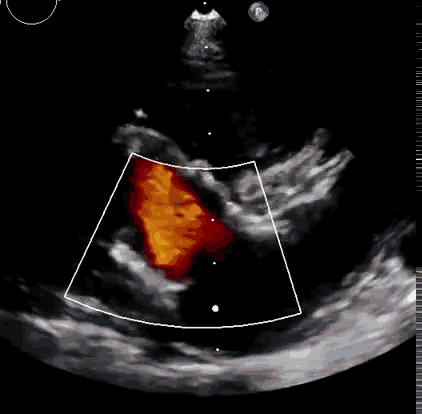

2021年11月14日星期日,復(fù)旦大學(xué)附屬中山醫(yī)院(以下簡稱中山醫(yī)院)葛均波院士團(tuán)隊(duì)成功應(yīng)用經(jīng)血管介入三尖瓣置換產(chǎn)品Lux-Valve Plus完成臨床前研究,并獲得圓滿成功!此次研究的成功預(yù)示經(jīng)血管三尖瓣產(chǎn)品Lux-Valve Plus已完成臨床前準(zhǔn)備,即將開啟后期的正式臨床研究!

上海中山醫(yī)院葛均波院士、錢菊英院長、周達(dá)新教授、潘文志教授、潘翠珍教授、李偉教授共同完成此次臨床前研究。術(shù)后葛均波院士對Lux-Valve Plus的器械操作性能給予了高度評價(jià),DSA和超聲影像也顯示出在本次研究中Lux-Valve Plus的安全性和有效性俱佳。

本次臨床前研究經(jīng)右側(cè)頸靜脈置入LuX-Valve Plus輸送系統(tǒng)可調(diào)彎鞘管,在DSA及超聲引導(dǎo)下將人工三尖瓣瓣膜植入到原有三尖瓣位置,利用獨(dú)特的錨定技術(shù)將人工瓣膜支架可靠固定在預(yù)定的位置。

Lux-Valve是全球第一款具有我國完全自主知識產(chǎn)權(quán)的經(jīng)導(dǎo)管介入三尖瓣置換系統(tǒng),利用前瓣夾持及室間隔錨定的復(fù)合方式進(jìn)行瓣膜裝置的固定,不依賴瓣環(huán)徑向支撐力,同時(shí)采用自適應(yīng)復(fù)合裙邊材料,有效的貼合密封柔軟的三尖瓣瓣環(huán),針對于三尖瓣返流的患者有優(yōu)異的療效。Lux-Valve Plus采用全新的經(jīng)血管輸送系統(tǒng),經(jīng)頸靜脈入路創(chuàng)傷更小,可以進(jìn)一步降低手術(shù)風(fēng)險(xiǎn)。相信在后期正式臨床研究開展中,Lux-Valve Plus必定會為更多的三尖瓣反流患者帶來福音。